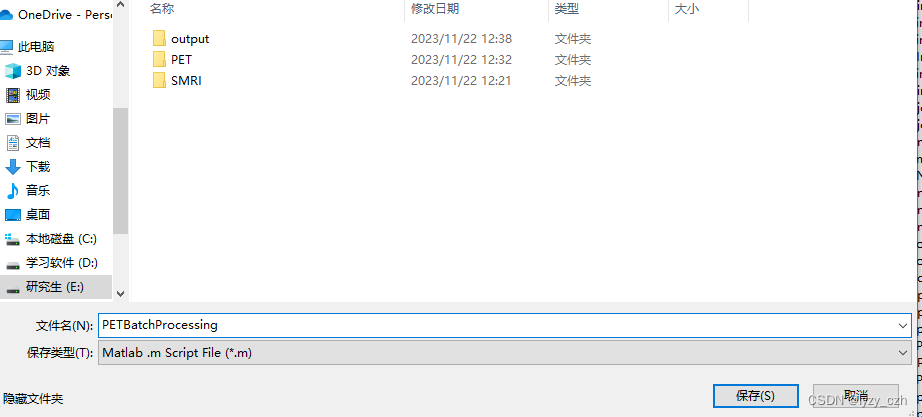

4、生成batch脚本

选择保存脚本的路径

点击保存后,会生成两个.m文件并且自动在matlab打开脚本文件如下: